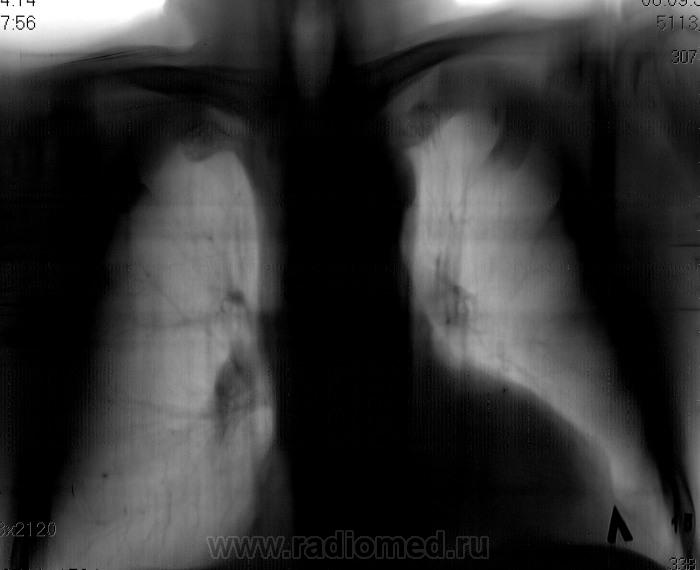

Не ясный...  В клинике превалирует одышка...

Более контрастные изображения.

Отмечает внезапно возникшую одышку? ЭХО-КГ было? Мне чудится симптом Вестермарка в верхней доле справа и нежная интерстициальная инфильтрация в S6 справа. Хвост правого корня не красивый, может он "обрублен"? Ну и признаки ХОБЛ есть.

Тень сердца объясняет причину одышки.

Коллеги, а как Вы объясните эту тень? Что-то я на ней зависла. Не ателектаз, не междолевой плеврит. Абдоминомедиастинальная липома?

Тень это жир, по прямому тоже хорошо видно что сердце жирновато

Попробую объяснить. Стрелок на картинках не нарисую, по причине что я сейчас однорукая (отдыхаю на больничном со сломаной правой). Я не настаиваю на своем мнении, мне только "почудилось". Если сравнивать лег рисунок верхних долей, то справа он мне кажется обедненным. Для такого-то сердца и сосудов по лег полям должно быть поболее. А интерстиц инфильтрация, потому что нет "пятен" и "хлопьев" сливающейся альвелярной (простите КТ-шный термин), а есть нежное сетчатое затемнение, на фоне которого прослеж сосуды. Вот дисковидных коллапсов я не нашла, покажете?

Насчет ХОБЛ - стенки бронхов утолщены муфтой, хрящевые кольца трахеи, главных, долевых и устьев сегментарных кальцинированы, это отлично видно на линейках.

У такого человека в возрасте мне кажется сейчас важнее всего как раз исключить ТЭЛА, ХОБЛ и застой это меньшее из зол.

Как-то сомневаюсь я в абдоминомедиастинальной липоме. Огроменные размеры, фестончатый контур. Подумала ещё о парастернальной диафрагмальной грыже. Валентин Львович, а в архиве что?